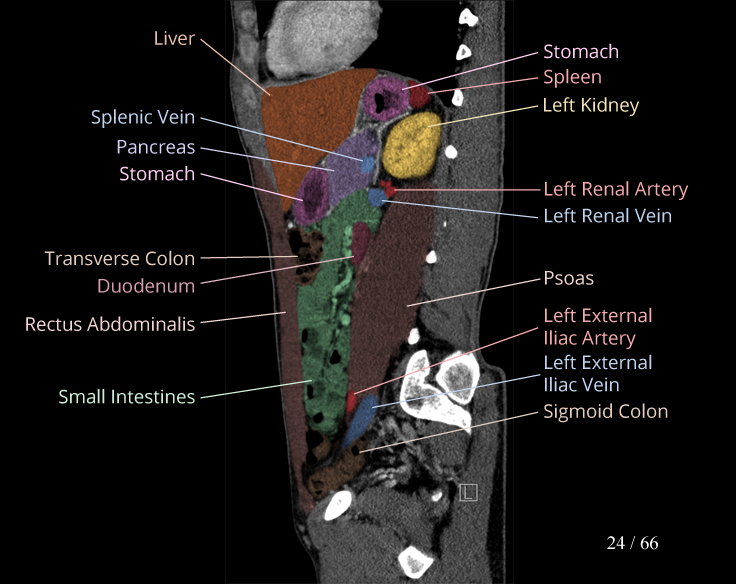

Body

Covers abdominal CT anatomy.